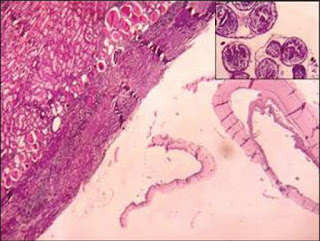

Microscopy shows laminated membranes of hydatid cyst with adjacent renal tissue showing compression and features of chronic pyelonephritis. (H and E, 100×). (Inset) Brood capsules showing scolices and lanceolate hooklets (H and E, 450×).

Impression: Isolated renal hydatid cyst.